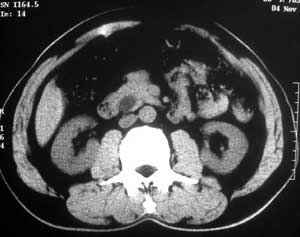

患者,男,57岁,梗阻性黄疸10余天。

这个病例胰头无明显增大,胆总管扩张明显而肝内胆管扩张更不明显,病程较短,

注意到十二指肠乳头明显突出,但尚光滑。分析以下可能性:

1、十二指肠乳头本身的病变,如乳头炎症;

2、急性乳头水肿,胆总管下端结石排石后乳头水肿;

3、壶腹部胆总管下端肿瘤累及十二指肠乳头。

十二指肠乳头粘膜慢性非特异性炎症